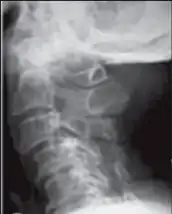

| Image,lateral view shows cervical spondylotic myelopathy | |

Myelopathy is any neurologic deficit related to the spinal cord.[1] When due to trauma, it is known as (acute) spinal cord injury. When inflammatory, it is known as myelitis. Disease that is vascular in nature is known as vascular myelopathy. The most common form are cervical spondylotic myelopathy (CSM),[2][3] also called degenerative cervical myelopathy[4] and is caused by arthritic changes (spondylosis) of the cervical spine, which result in narrowing of the spinal canal ultimately causing compression of the spinal cord.[5] In Asian populations, spinal cord compression often occurs due to a different, inflammatory process affecting the posterior longitudinal ligament.